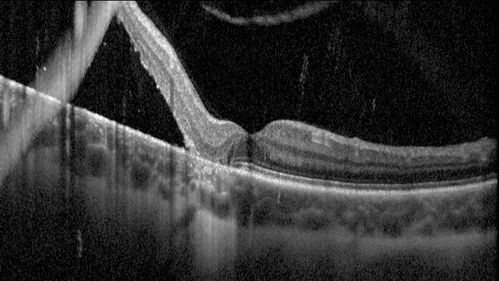

Chronic macula-splitting demarcated retinal detachment

35 year old female with 20/25 vision and noticing something wrong with the superior vision in the right eye for a long time.